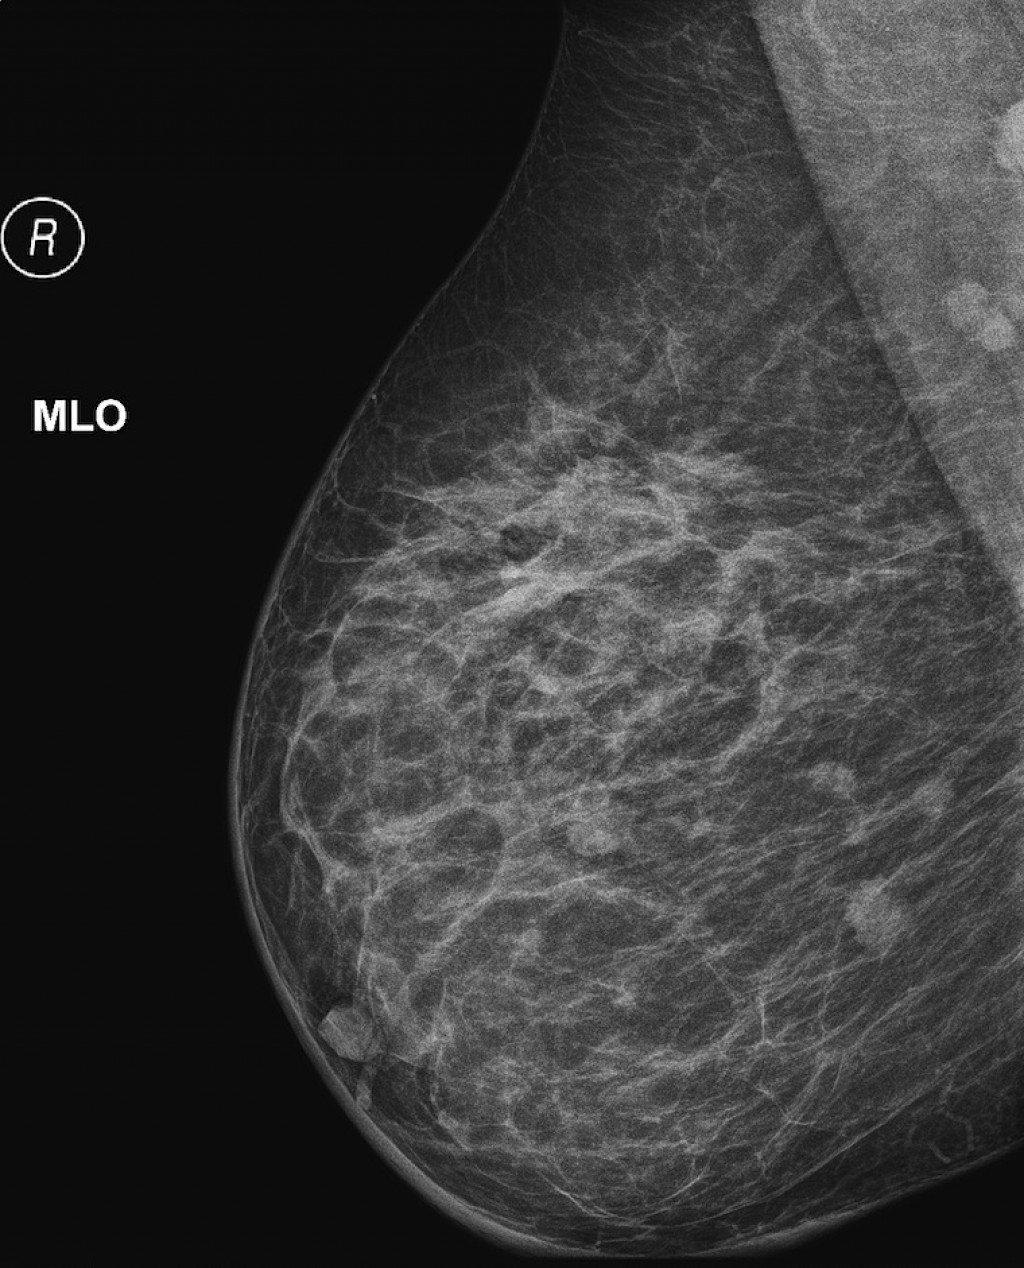

УЗИ молочных желез — информативный и безопасный метод диагностики, с помощью которого можно точно оценить состояние желез, обнаружить доброкачественные и злокачественные образования, уточнить диагноз. Это доступное по цене исследование безвредно и не несет лучевой нагрузки. Оно имеет большое значение в ранней диагностике заболеваний и нередко применяется в профилактических целях. На УЗИ может направить маммолог, онколог, эндокринолог, гинеколог.

При отсутствии жалоб проходить УЗИ необходимо пациенткам возрастом 25–39 лет один раз в два года, старше 40 — ежегодно. УЗИ молочных желез после 40 лет важно проводить регулярно с целью профилактики онкологических заболеваний. Гормональные изменения, связанные с возрастными процессами, повышают риск появления новообразований.

Сделать УЗИ молочных желез можно в качестве первичной диагностики и для уточнения уже предполагаемого диагноза. Метод основывается на способности высокочастотных ультразвуковых волн с различной скоростью отражаться от тканей с разной плотностью.

С помощью ультразвуковой диагностики можно обнаружить следующие заболевания:

- рак;

Кому противопоказано

УЗИ практически не имеет противопоказаний. Однако важно отметить, что информативность обследования груди таким способом у женщин молодого возраста выше, поскольку ткани молочных желез с возрастом становятся более рыхлыми. Поэтому после 40 лет УЗИ в большинстве случаев сочетается с рентген-диагностикой (маммографией).